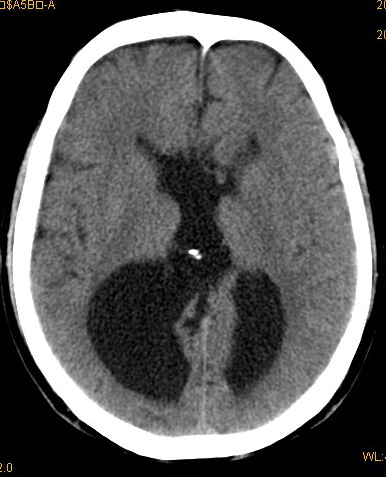

以下是引用卜一在2008-8-14 16:31:00的发言:[br]支持:巨脑回伴脑积水!另:胼胝体发育不良!

以下是引用随光逐影在2008-8-14 16:58:00的发言:[br]胼胝体发育不良;脑积水。

以下是引用同在2008-8-14 19:46:00的发言:[br]巨脑回伴积水,胼胝体发育不良.